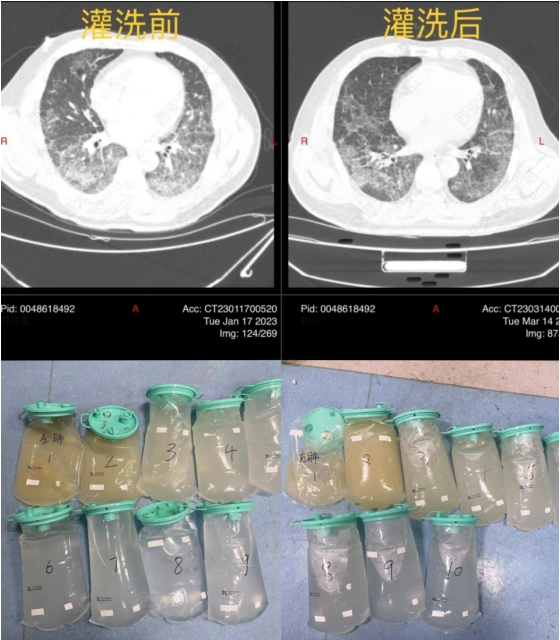

病例3:危重的肺泡蛋白沉积症

患者,男性,39岁,双肺弥漫性间质性炎(图14)PaO53 mmHg、Ⅰ型呼吸衰竭,高流量吸氧及无创呼吸机辅助通气无明显改善,收住RICU,行冷冻肺活检提示:肺泡蛋白沉积症(图15)

MDT意见:难以纠正的呼吸衰竭;肺功能差;灌洗过程中可能出现急性肺水肿;难以耐受长时间全身麻醉。予清醒VV-ECMO+大容量肺泡灌洗。患者氧合得以纠正,病情好转(图16)

图16  患者肺泡灌洗前后比较

思考:①对于双肺弥漫性间质性病变患者,明确诊断非常关键。受目前医疗技术的限制,冷冻肺活检是各指南共识均推荐的重要方法,在危重症患者的救治过程中,不要因为此项技术有较大的出血风险就放弃,而需要依据操作流程,细心、大胆,尽可能为患者明确诊断,争取治疗时机。②此例是在ECMO支持下为患者争取了救治机会,经第一次双肺大容量灌洗后,氧合明显改善,后续治疗不再依赖ECMO进行。